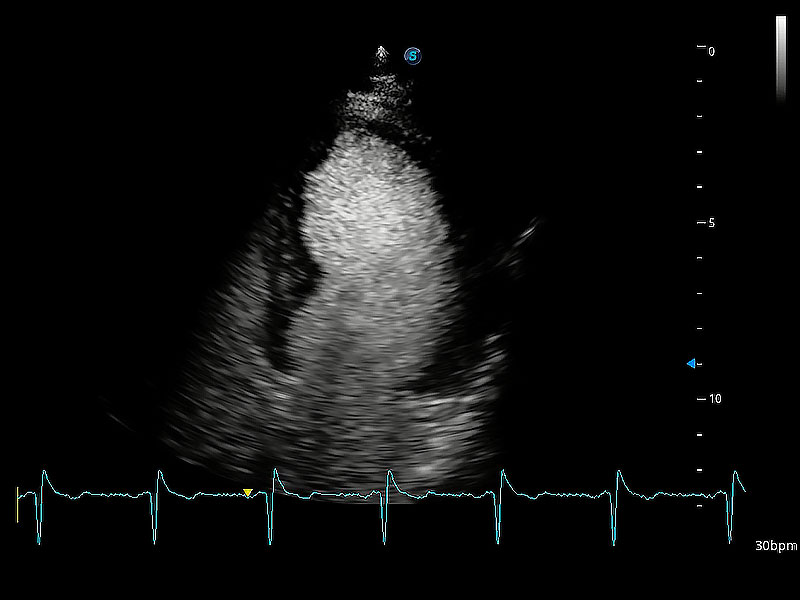

ProPet 80 配備了豐富的心臟探頭群、先進(jìn)的成像技術(shù)和專業(yè)的心臟測量工具,可幫助動物醫(yī)生為不同體型和生理結(jié)構(gòu)的動物提供心臟和心肌功能的全面評估。

實時用顏色表示心肌組織運(yùn)動,觀察和定量組織的運(yùn)動情況,對快速檢測與評估心肌的灌注和活性、電傳導(dǎo)及心肌收縮和舒張功能等均能提供重要的診斷信息。